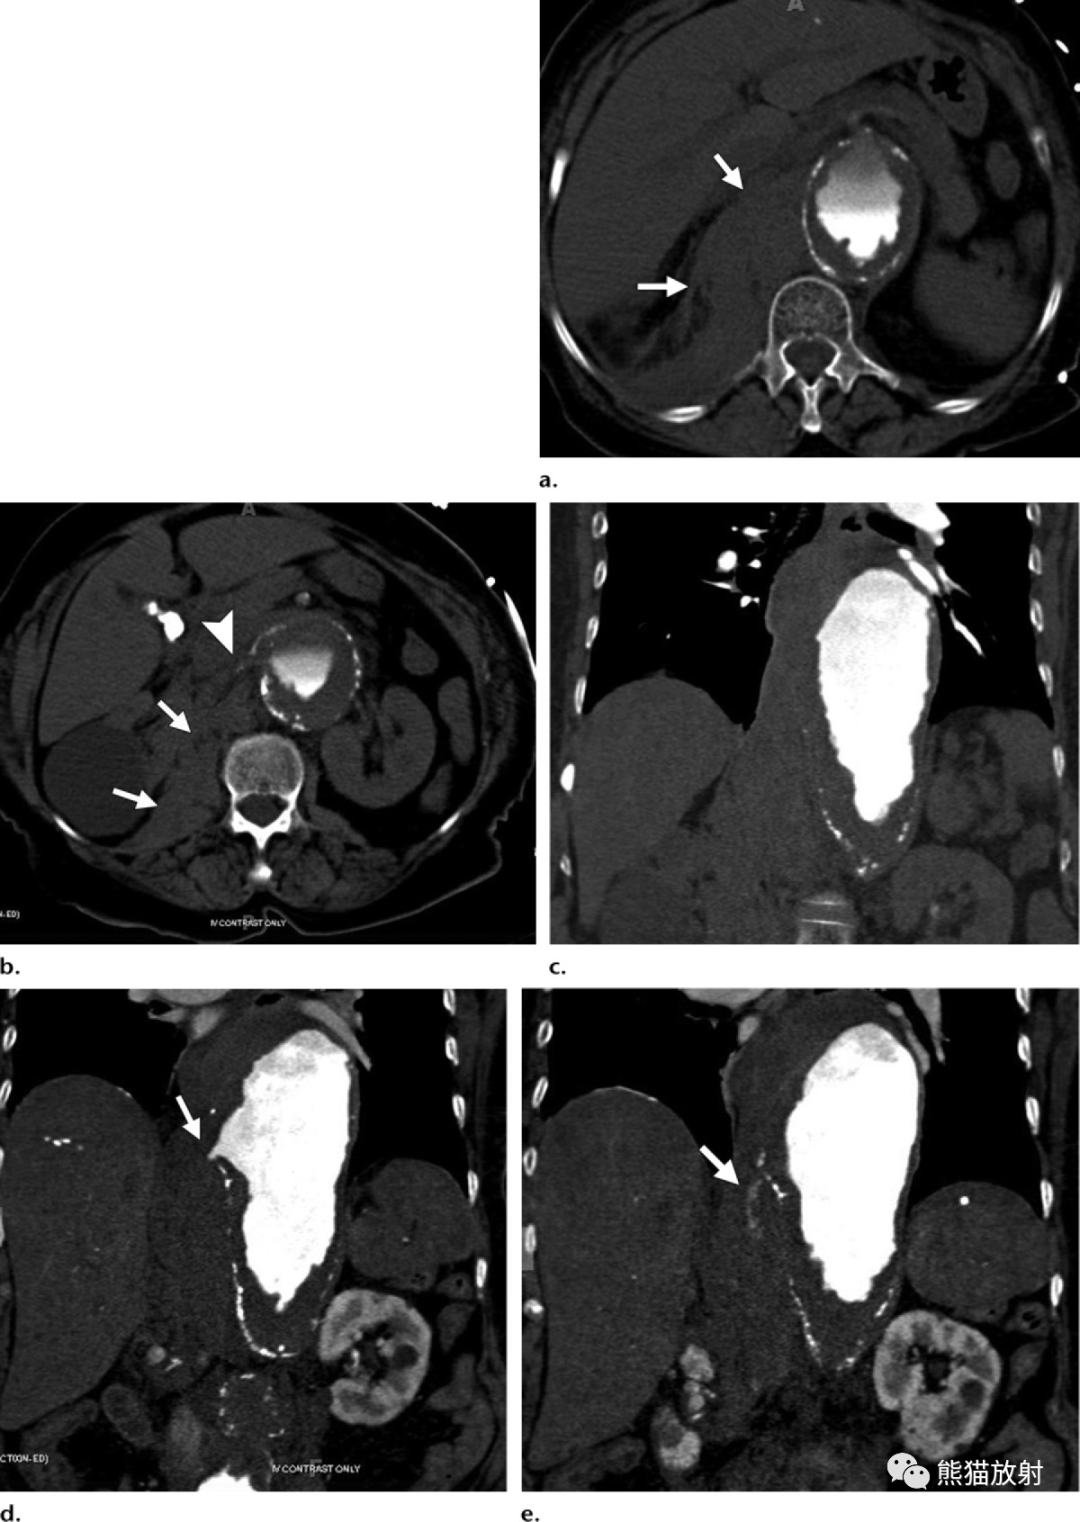

巨大腹主动脉夹层动脉瘤?

破裂腹主动脉瘤腔内治疗一例

腹主动脉瘤破裂!

急诊胸腹主动脉cta检查可见腹主动脉瘤